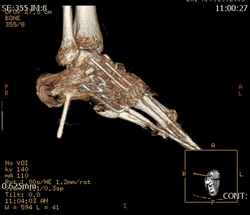

At 28 and already having sixteen surgical procedures behind me, life was not going as I had planned. I had left three jobs in the last year, one which I really loved, all because of the severe foot pain that I lived with everyday. The cause of the pain made a solution especially difficult. I had a congenital neuropathy called, Charcot Marie Tooth Disease, and a bone disease known as, Osteogenesis Imperfecta, along with many serious injuries over the past ten years making mine an especially complicated case. My body felt much older than it's young looks betrayed.

I was referred to Doctor Leavitt at the very beginning of 2008. When I met Dr. Leavitt for the first time I left knowing two things. First, my case would be difficult and even impossible for most surgeons (in fact many doctor's in the past refused to operate on me because of the complicated nature of my case). Second, Dr. Leavitt was the right man. I've never left a consultation feeling both so overwhelmed at what was in store for me in terms of pain, recovery, and rehab and yet so at ease that I was in the most capable hands. To say Dr. Leavitt is thorough would be an understatement. In fact, I had four visits in the month leading up to my surgery and I even received a phone call on a Sunday afternoon from Dr. Leavitt to confirm something he was working on at home. I took comfort knowing that I was going into a situation that had been planned out down to every detail and every contingency was accounted for. Simply put, Doctor Leavitt is the most accessible and capable doctor I have ever met.